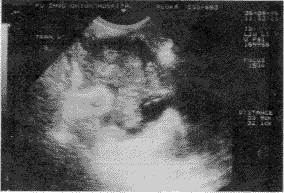

2.经阴道超声直肠癌声像表现:本组直肠癌声像表现可分为3型:(1)浸润型:病变段肠壁广泛增厚,此型多伴有肠腔狭窄(图2);(2)隆起型:病变呈宽基底的实体团块状隆向肠腔(图3);蕈伞型:病变呈菜花状突向肠腔,其基底相对较窄(图4)。上述三型尤其是隆起型和蕈伞型,其表面常见溃疡,声像表现为溃疡部中心凹陷,边缘隆起,溃疡面呈强光斑、光点回声。

左图示病变累及二分之一肠周径。右图示病变致肠腔狭窄伴肠周淋巴结转移

图2 经阴道超声直肠癌(C期浸润型)声像图